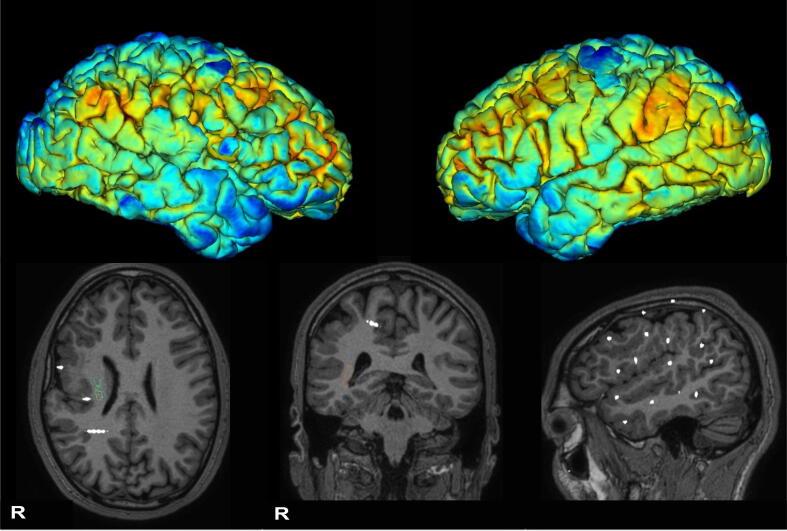

Radiofrequency thermocoagulation (RF-TC) is a wide-used procedure for drug-resistant epilepsy. The technique is considered safe with an overall risk of 1.1% of permanent complications, mainly focal neurological deficits. We report the case of a patient with drug-resistant epilepsy who complained of immediate seizure worsening and an unexpected event seven months following RF-TC. A 35-year-old male with drug-resistant epilepsy from the age of 18 years underwent stereoelectroencephalography (SEEG) implantation for a right peri-silvian polymicrogyria. He was excluded from surgery due to extent of the epileptogenic zone and the risk of visual field deficits. RF-TC was attempted to ablate the most epileptogenic zone identified by SEEG. After RF-TC, the patient reported an increase in seizure severity/frequency and experienced episodes of postictal psychosis. Off-label cannabidiol treatment led to improved seizure control and resolution of postictal psychosis. Patients with polymicrogyria (PwP) may present with a disruption of normal anatomy and the co-existence between epileptogenic zone and eloquent cortex within the malformation. RF-TC should be considered in PwP when they are excluded from surgery for prognostic and palliative purposes. However, given the complex interplay between pathological and electrophysiological networks in these patients, the remote possibility of clinical exacerbation after RF-TC should also be taken into account.

射频热凝术(RF-TC)是一种广泛应用于耐药性癫痫的治疗方法。该技术被认为是安全的,永久性并发症的总体风险为1.1%,主要是局灶性神经功能缺损。我们报告了一例耐药性癫痫患者的病例,该患者在RF-TC治疗七个月后出现癫痫发作立即恶化以及一个意外事件。一名35岁男性,自18岁起患有耐药性癫痫,因右侧颞叶周围多小脑回畸形接受了立体定向脑电图(SEEG)植入术。由于致痫区范围和视野缺损风险,他被排除在手术之外。尝试通过RF-TC消融SEEG确定的最致痫区。RF-TC治疗后,患者报告癫痫发作严重程度/频率增加,并出现发作后精神病发作。超说明书使用大麻二酚治疗使癫痫得到更好的控制,并解决了发作后精神病。多小脑回畸形患者(PwP)可能存在正常解剖结构破坏,且畸形内致痫区与功能区皮质并存。当PwP因预后和姑息目的被排除在手术之外时,应考虑RF-TC治疗。然而,鉴于这些患者病理和电生理网络之间复杂的相互作用,也应考虑RF-TC治疗后临床症状加重的可能性。